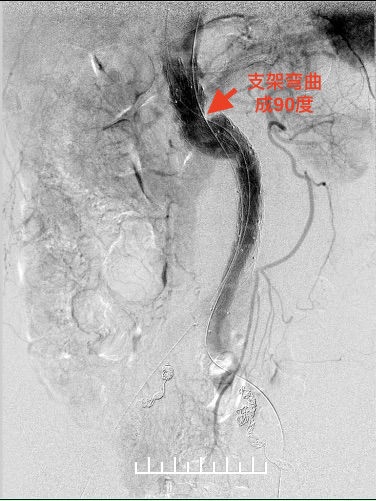

1.此病例腹主动脉扭曲严重,瘤颈成角90度,不符合报道的解剖标准:瘤颈长度≥10 mm、瘤颈成角≤75度。

使用全穿刺技术(Preclose技术),建立双侧股动脉及右侧肱动脉入路。“全身像”显示:瘤颈成角约90度,左侧髂总动脉钙化扭曲严重,双侧髂内动脉显影,左侧髂内动脉瘤。

右侧超硬导丝到位,试图纠正瘤颈角度,结果不佳。支架必须使用柔顺性较好的,美敦力(28mm-16mm*160mm,Endurant II)是较好的选择。

支架柔顺性好,这是信心的来源。